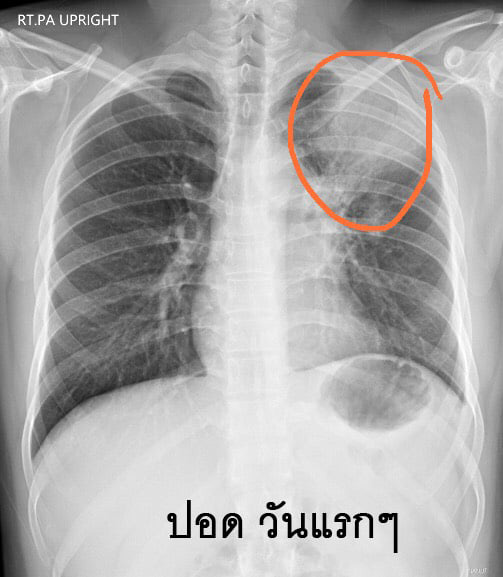

วันที่ 18 มิถุนายน 2563 เฟซบุ๊ก Chayanin Wisutthikul ได้แชร์ประสบการณ์ของเพื่อนคนหนึ่งที่ไอเป็นเลือด รักษากว่า 5 เดือน ตั้งแต่วันที่ 17 มกราคม 2563 เข้า-ออกโรงพยาบาล 3-4 แห่ง เบื้องต้นไปรักษาที่โรงพยาบาลที่ทำประกันสังคม แต่อาการไม่ดีขึ้น จึงไปรักษาที่คลินิกก็ได้ใบส่งตัวทำ CT SCAN เพราะมีการเอกซเรย์เบื้องต้น นอกจากจะเจอฝ้าที่ปอดแล้ว ยังเจอก้อนขาวกลางหน้าอก แพทย์ที่คลินิกกังวลว่าจะเป็นชิ้นเนื้อ จึงทำใบส่งตัวให้ไป CT SCAN ที่โรงพยาบาลประกันสังคม เพื่อช่วยเซฟค่าใช้จ่าย

แต่เมื่อเพื่อนไปถึงโรงพยาบาลประกันสังคม แพทย์และพยาบาลก็ไม่ได้สนใจใบส่งตัวทำ CT SCAN แต่ได้ให้ยาฆ่าเชื้อปอดอักเสบมา หลังจากผ่านไป 1 สัปดาห์ ก็ไม่พบว่ามีฝ้าที่ปอดแล้ว หมอก็บอกว่าไม่มียาให้แล้ว หายแล้ว กลับบ้านได้ เมื่อเพื่อนชี้ให้ดูที่หน้าจอเอกซเรย์ บอกว่าคลินิกที่ไปมาก่อนหน้านี้บอกว่าเป็นชิ้นเนื้อ แต่ทางหมอตอบกลับมาว่าเป็นเส้นเลือดใหญ่

ต่อมาเพื่อนก็กลับมาใช้ชีวิตปกติ เพราะหมอบอกว่าหายแล้ว แต่อาการไอไม่ดีขึ้นเลย แค่ไม่มีเลือดแล้ว เจ้านายจึงแนะนำแกมบังคับอีกรอบว่าให้ไป CT SCAN ที่ศูนย์แพทย์ซะ จะได้รู้ให้จบ ๆ ว่าเป็นอะไร เพื่อนก็เลยโทร. นัดแพทย์ที่คลินิกแพทย์อีกครั้ง และได้ทำ CT SCAN ในวันที่ 24 มีนาคม 2563 ผลออกมาว่า จุดขาว ๆ ที่กลางหน้าอกคือเนื้องอก ที่ตอนนี้มีขนาดความยาว 9x8x7 cm (ขนาดประมาณเท่ากำปั้น) หลังจากนั้นแพทย์ก็เขียนใบส่งตัวให้ไปรักษาที่โรงพยาบาลประกันสังคม (เพื่อนทำเรื่องเปลี่ยนโรงพยาบาลประกันสังคมแล้ว)